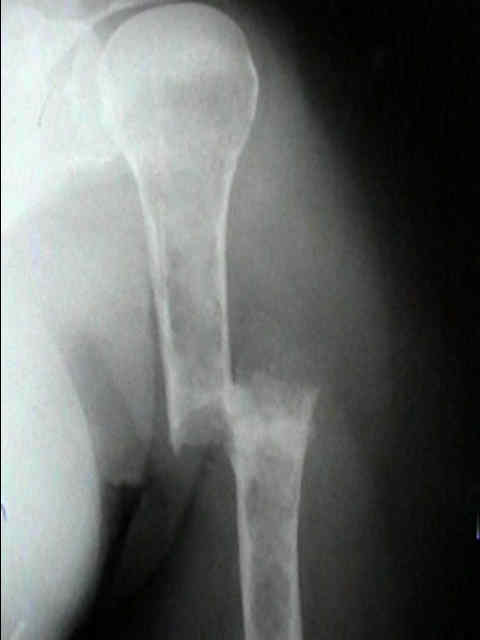

Radiographic Studies

- standard x-rays may show diffuse osteopenia

- "punched-out lesions" w/ no surrounding new-bone formation;

- over time lesions may change from diffuse osteopenia to more permeative moth-eaten destructive pattern, sometimes w/ cortical expansion;

- bone destruction occurs w/ little or no reactive bone formation unless pathologic frx is present;

- myeloma may present as solitary lesion or more commonly a diffuse tumor, involving multiple bones, including vertebrae, skull, pelvis and femurs;

Surgical Fixation

- Treatment of pathologic fracture of the humerus.